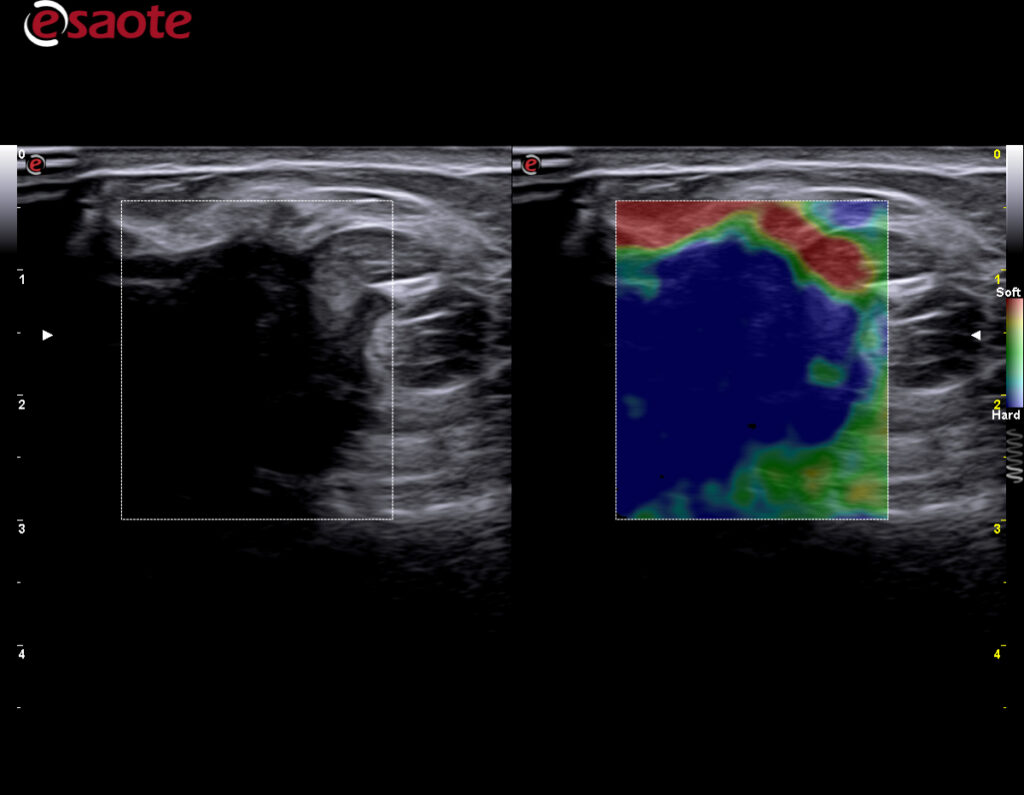

Kliniske bilder.

ElaXto

ElaXto (strain) lisens gir deg mulighet til å evaluere stivheten i et valgt område i real-time. Esaote har vært en pioner og stått fremst innenfor dette feltet i mange år. Dette benyttes innenfor mange områder som MSK, Bryster og Tyridea, Lever, Urologi(prostata) og gynekologi. -

ElaXto advanced

Advanced ElaXto et tilvalg til ElaXto lisensen -